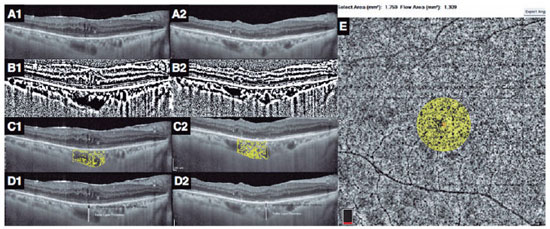

In each eye, the horizontal EDI-OCT scan passing through the fovea was selected for image analyses (Figure 1A1). Postoperatively, the EDI-OCT scan was matched to the one passing through the central foveal segment at baseline (Figure 1A2). The central choroidal thickness was determined as the distance between the lower boundary of the retinal pigment epithelium and the choroid-scleral interface(10). The CVI was computed as the ratio of the luminal area to the total choroidal area. The images were converted to 8 bits, and image thresholding adjustment was applied using ImageJ (version 1.47, National Health Institute, Bethesda, MA, USA) to highlight the vascular lumens (Figure 1B1 and B2). The choroidal area in OCT scans was binarized as reported in the literature(11). Then, each binarized image was converted to the RGB format, and luminal areas were highlighted using the color thresholding tool (Figure 1C1 and C2). The total choroidal, luminal, and stromal areas were calculated within the central 1500 μm. Bright pixels were defined as the choroidal interstitial area, whereas dark pixels were defined as the vascular luminal area(3,11).

The choroidal vascular layers were segmented manually. Measurements were performed by two graders, and the mean difference between their measurements was 4.4% ± 1.9% (range, 3%-8%). The Haller layer was delineated as the outer zone of choroidal vessels that were >100 μm(10). The H/C ratio was defined as the ratio of the Haller layer to the total choroidal thickness (Figure 1 D1 and D2)(4).

OCT-A measurements

The 6 × 6 mm OCT-A scans with a signal strength index ≥60 and without any motion artifact were used for analysis. OCT segmentation was automatically performed using the integrated module. The vascular densities of the inner and superficial capillary plexuses, CF, and central foveal thickness were measured using an integrated software. The CF was measured as the ratio of the flow area to the non-flow area in a 750 μm-radius circle, which was centered at the fovea (Figure 1 E)(4).

In the literature, choroidal thickness was the first parameter to be studied related to ERM, and studies have reported contradictory results(14-17). The present study did not disclose any significant change in the choroidal thickness in ERM. However, the baseline central choroidal thickness in ERM eyes tended to be thinner than that in the healthy fellow eyes and appeared to increase postoperatively. These minor changes in choroidal thickness may imply the initial displacement of the foveal center by the ERM away from the choroidal central point-where the choroid is thickest-and a postoperative return toward its original location. Another consequence of this tractional displacement is that postoperative OCT images do not pass through the exact same section of the choroid (Figure 1A1 and A2) because consecutive OCT images are matched to the retinal landmarks of the baseline OCT image.